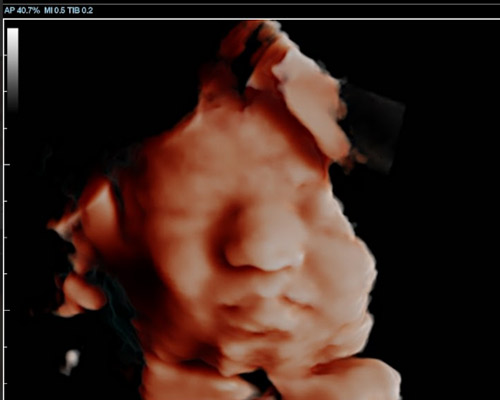

A 3D scan creates detailed still images showing your baby’s features, while a 4D baby scan allows you to see those images in motion. You may notice gentle movements, stretches, or even small expressions, which can make the experience feel much more real.

With a 4D baby ultrasound Huddersfield, this advanced imaging allows parents to see their baby in a way that feels closer to a photograph than a traditional scan.

- Clearer facial detail - improved definition and shape

- More natural visuals - Enhanced depth and tone

Our Scans